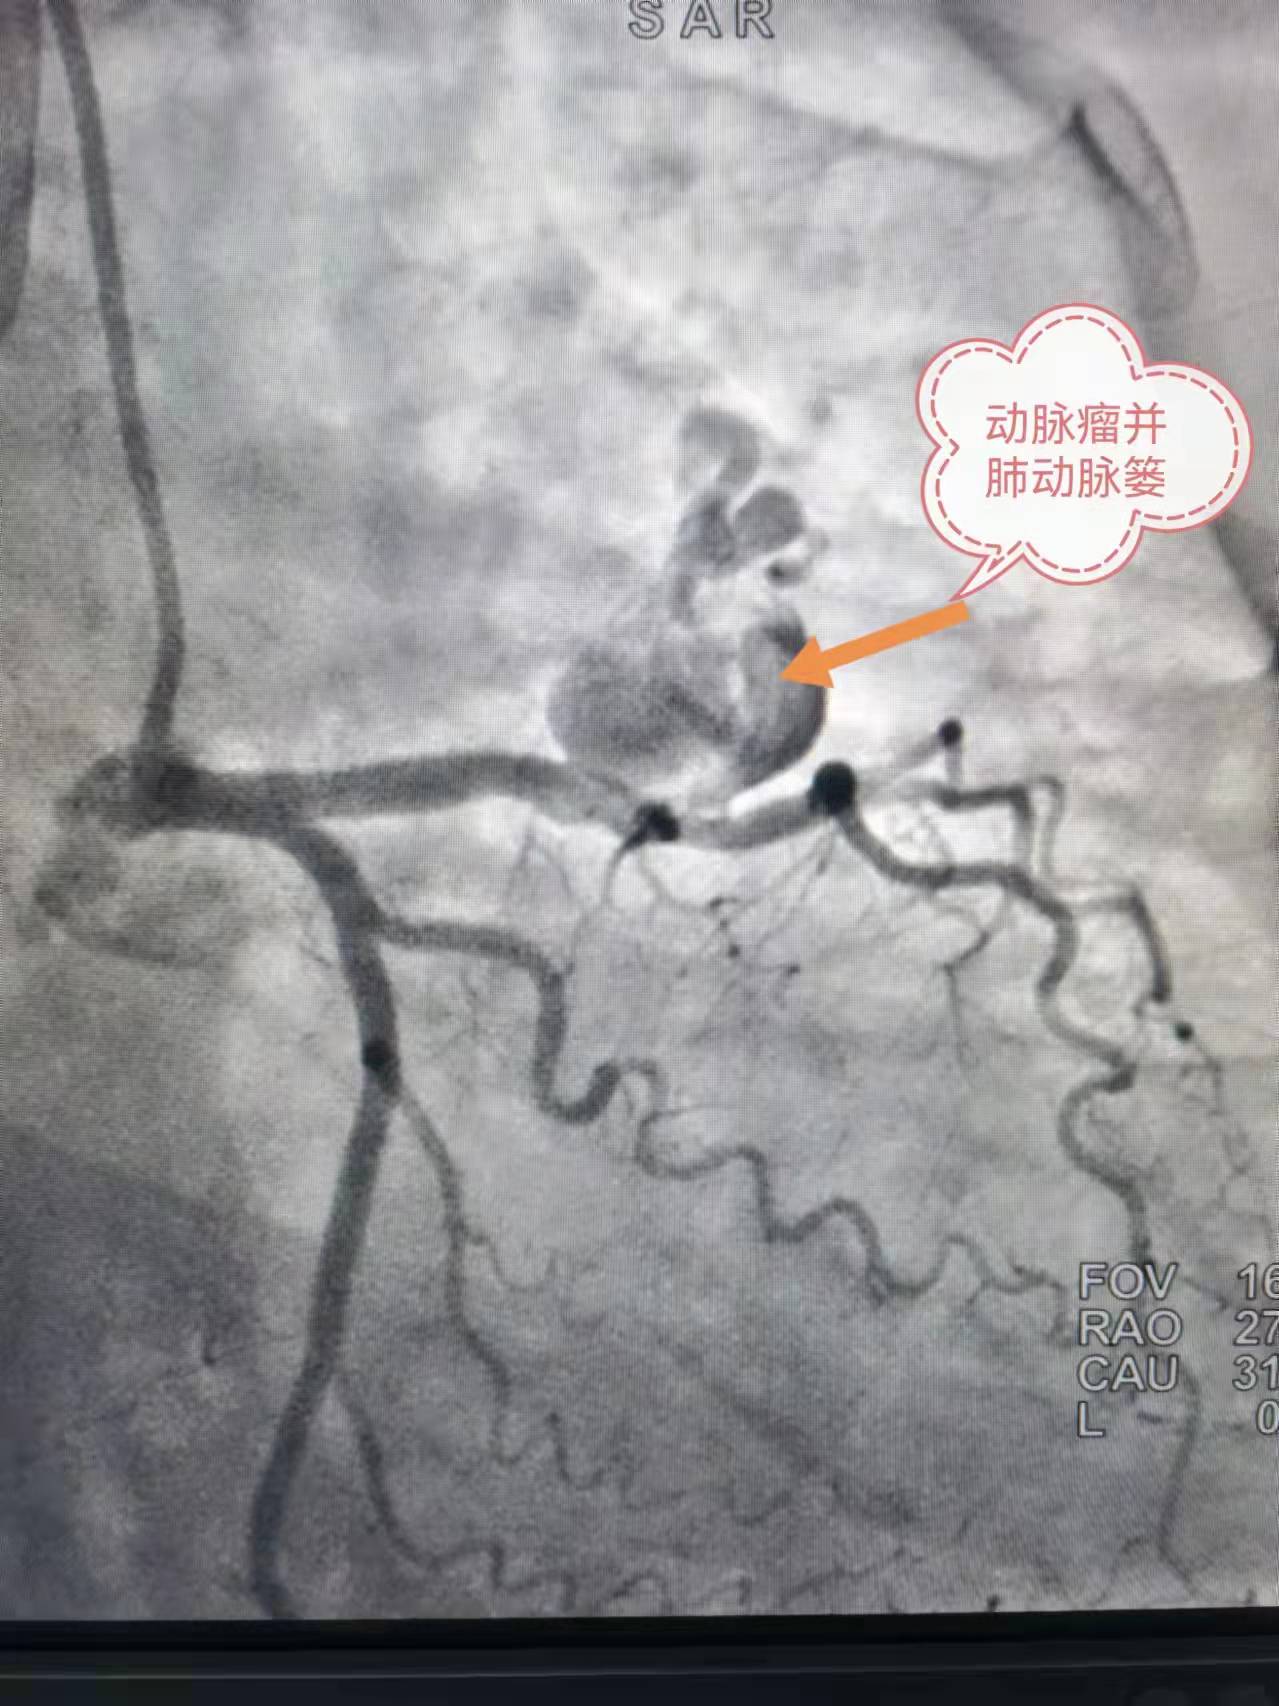

术前造影

57 岁的陶女士四年前反复出现胸背部阵发性胀痛,以夜间平躺时居多,开始未予重视。直到一个月前,上述症状加重,并伴有气短,在当地医院进一步检查后,确诊为巨大冠状动脉瘤伴肺动脉瘘。辗转多家医院就诊,均因病情复杂、手术风险大,被告知只能开胸手术。后经人介绍来到捷克论坛 岳麓山院区胸痛中心就诊。

胸痛中心主任欧柏青教授对患者进行充分评估,考虑其除巨大冠状动脉瘤,还合并肺动脉瘘,病情复杂,立即开展MDT(多学科诊疗)讨论,邀请心内科潘宏伟教授、介入血管外科向斌主任反复评估患者病情,研究造影影像,讨论并制定了严谨周密的手术方案。